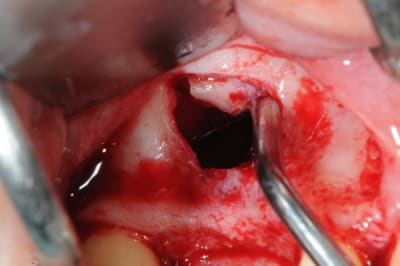

je sais pas si c'est un produit miracle, mais pour les sinus lift, c'est fantastique.

outre le fait de stabiliser un implant dans un sinus type SA4, pas de risque de voir partir le produit comme avec les granules de bioos et autres..

l'autre avantage est de ne pas avoir à mettre de membrane de recouvrement.

je suis donc hyper satisfait du résultat.

jugez plutôt...

l'application type du VitalOs, avec le bone splitting.

le protocole tel qu'il est d'écrit voudrait que l'on applique d'abord une couche de vital os en palatin - laisser durcir - mettre l'implant puis mettre une dernière couche.

ici, j'ai mis l'implant- maintenu la membrane de Schneider en poussant avec l'embout sur celle ci et terminer l'injection du produit. c'est l'un des avantages de ce produit, il est livré avec deux embouts donc les deux solutions sont possibles pour une même seringue.